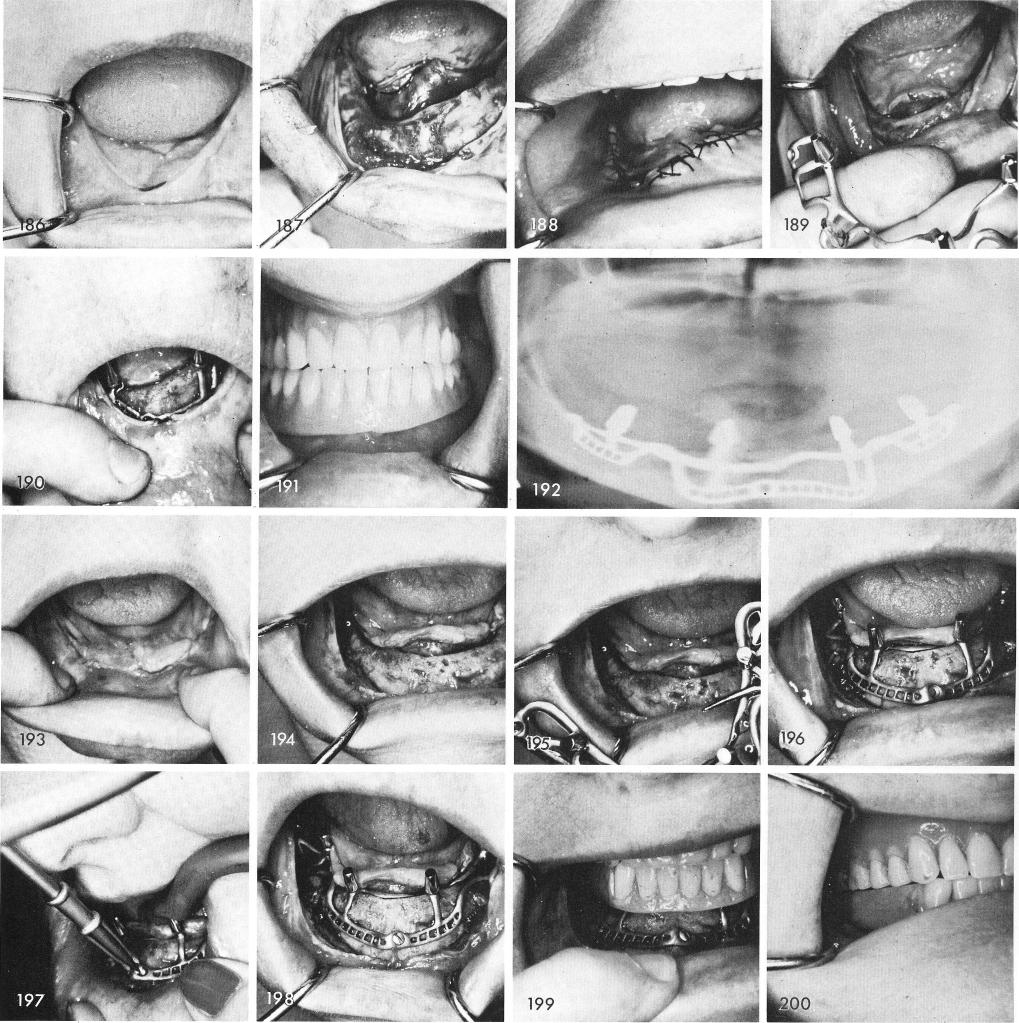

Asymmetrical mandibles, fig. 186, also can be indicated for subperiosteal implants as seen in figs. 187 through 192.

Even when the clinical picture makes it seem nearly impossible for a subperiosteal implant, fig. 193, when exposing the bone an entire new picture takes place, fig. 194. Figs. 195, 196 show the accurate fit of the implant and figs. 197 and 198 show the careful technique of fixating the